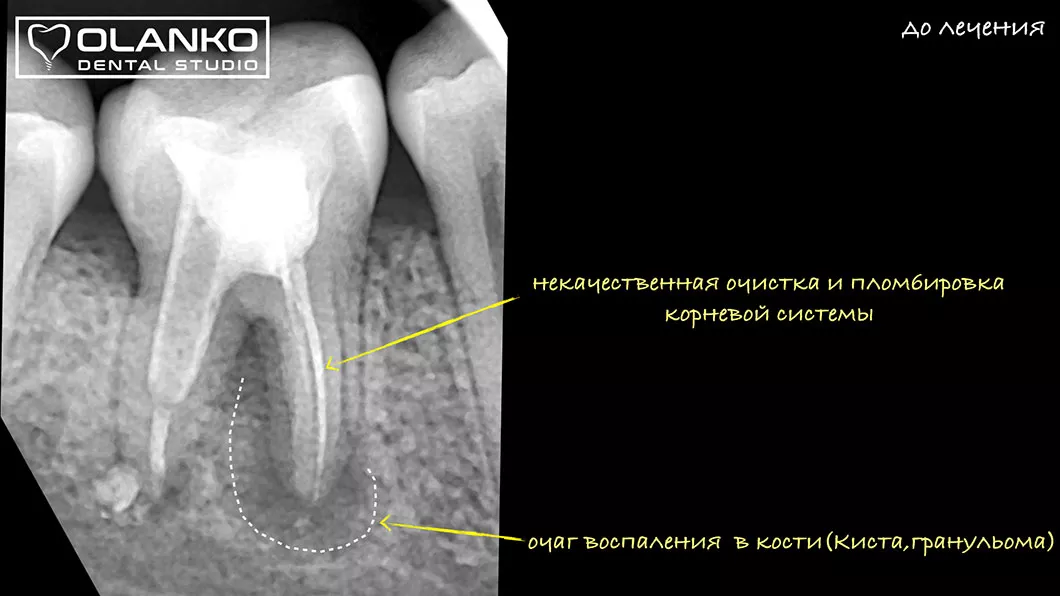

Ми маємо величезний клінічний досвід лікування зубів зі складною анатомією (викривленими, склерозованими каналами), а також повторного переліковування каналів з кістою, гранульомами, зламаними інструментами, з подальшими відмінними результатами загоєння хронічних запалень.

Апікальна(ендодонтична) мікрохірургія - це зубозберігаюча операція, яка проводиться в ділянці верхівки кореня зуба, за допомогою хірургічного доступу через кістку, при цьому видалється інфікована частина кореня і зуб герметично пломбується ретроградно, через хірургічну рану. Вся операція проходить з використанням дентального мікроскопу і біосумісних матеріалів.

Показами до данної операциї являються ті клінічні випадки, при яких стандартне ендодонтичне лікування кореневих каналів не далопозитивного результату далопозитивного результату або в зубі є блоки, які не дають, якісно обробити кореневий такі як сходинки, зламані інструменти, атипова анатомія.

Також показами є істинні кісти та інфекція поза кореневим каналом на які ми не можемо вплинути через консервативне ендодонтичне лікування.

Цей метод можна використовувати, якщо в зубі є велика штифтова конструкція або нова коронка і їхній демонтаж може суттєво пошкодити його.

Часто апікальна хірургія є єдиним способом уникнути видалення зуба.